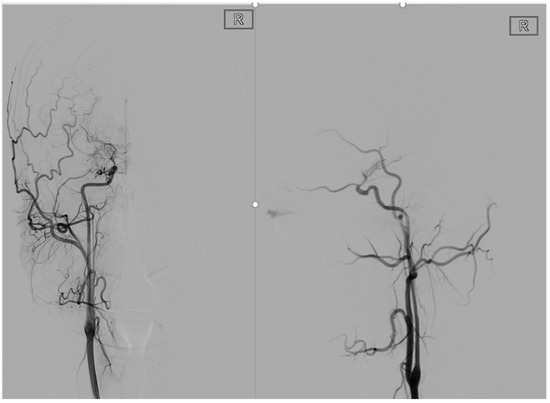

2.3.11. Factor 6 Unstable Compensation

2.3.12. Factor 7 Extracranial Arterial Compensation